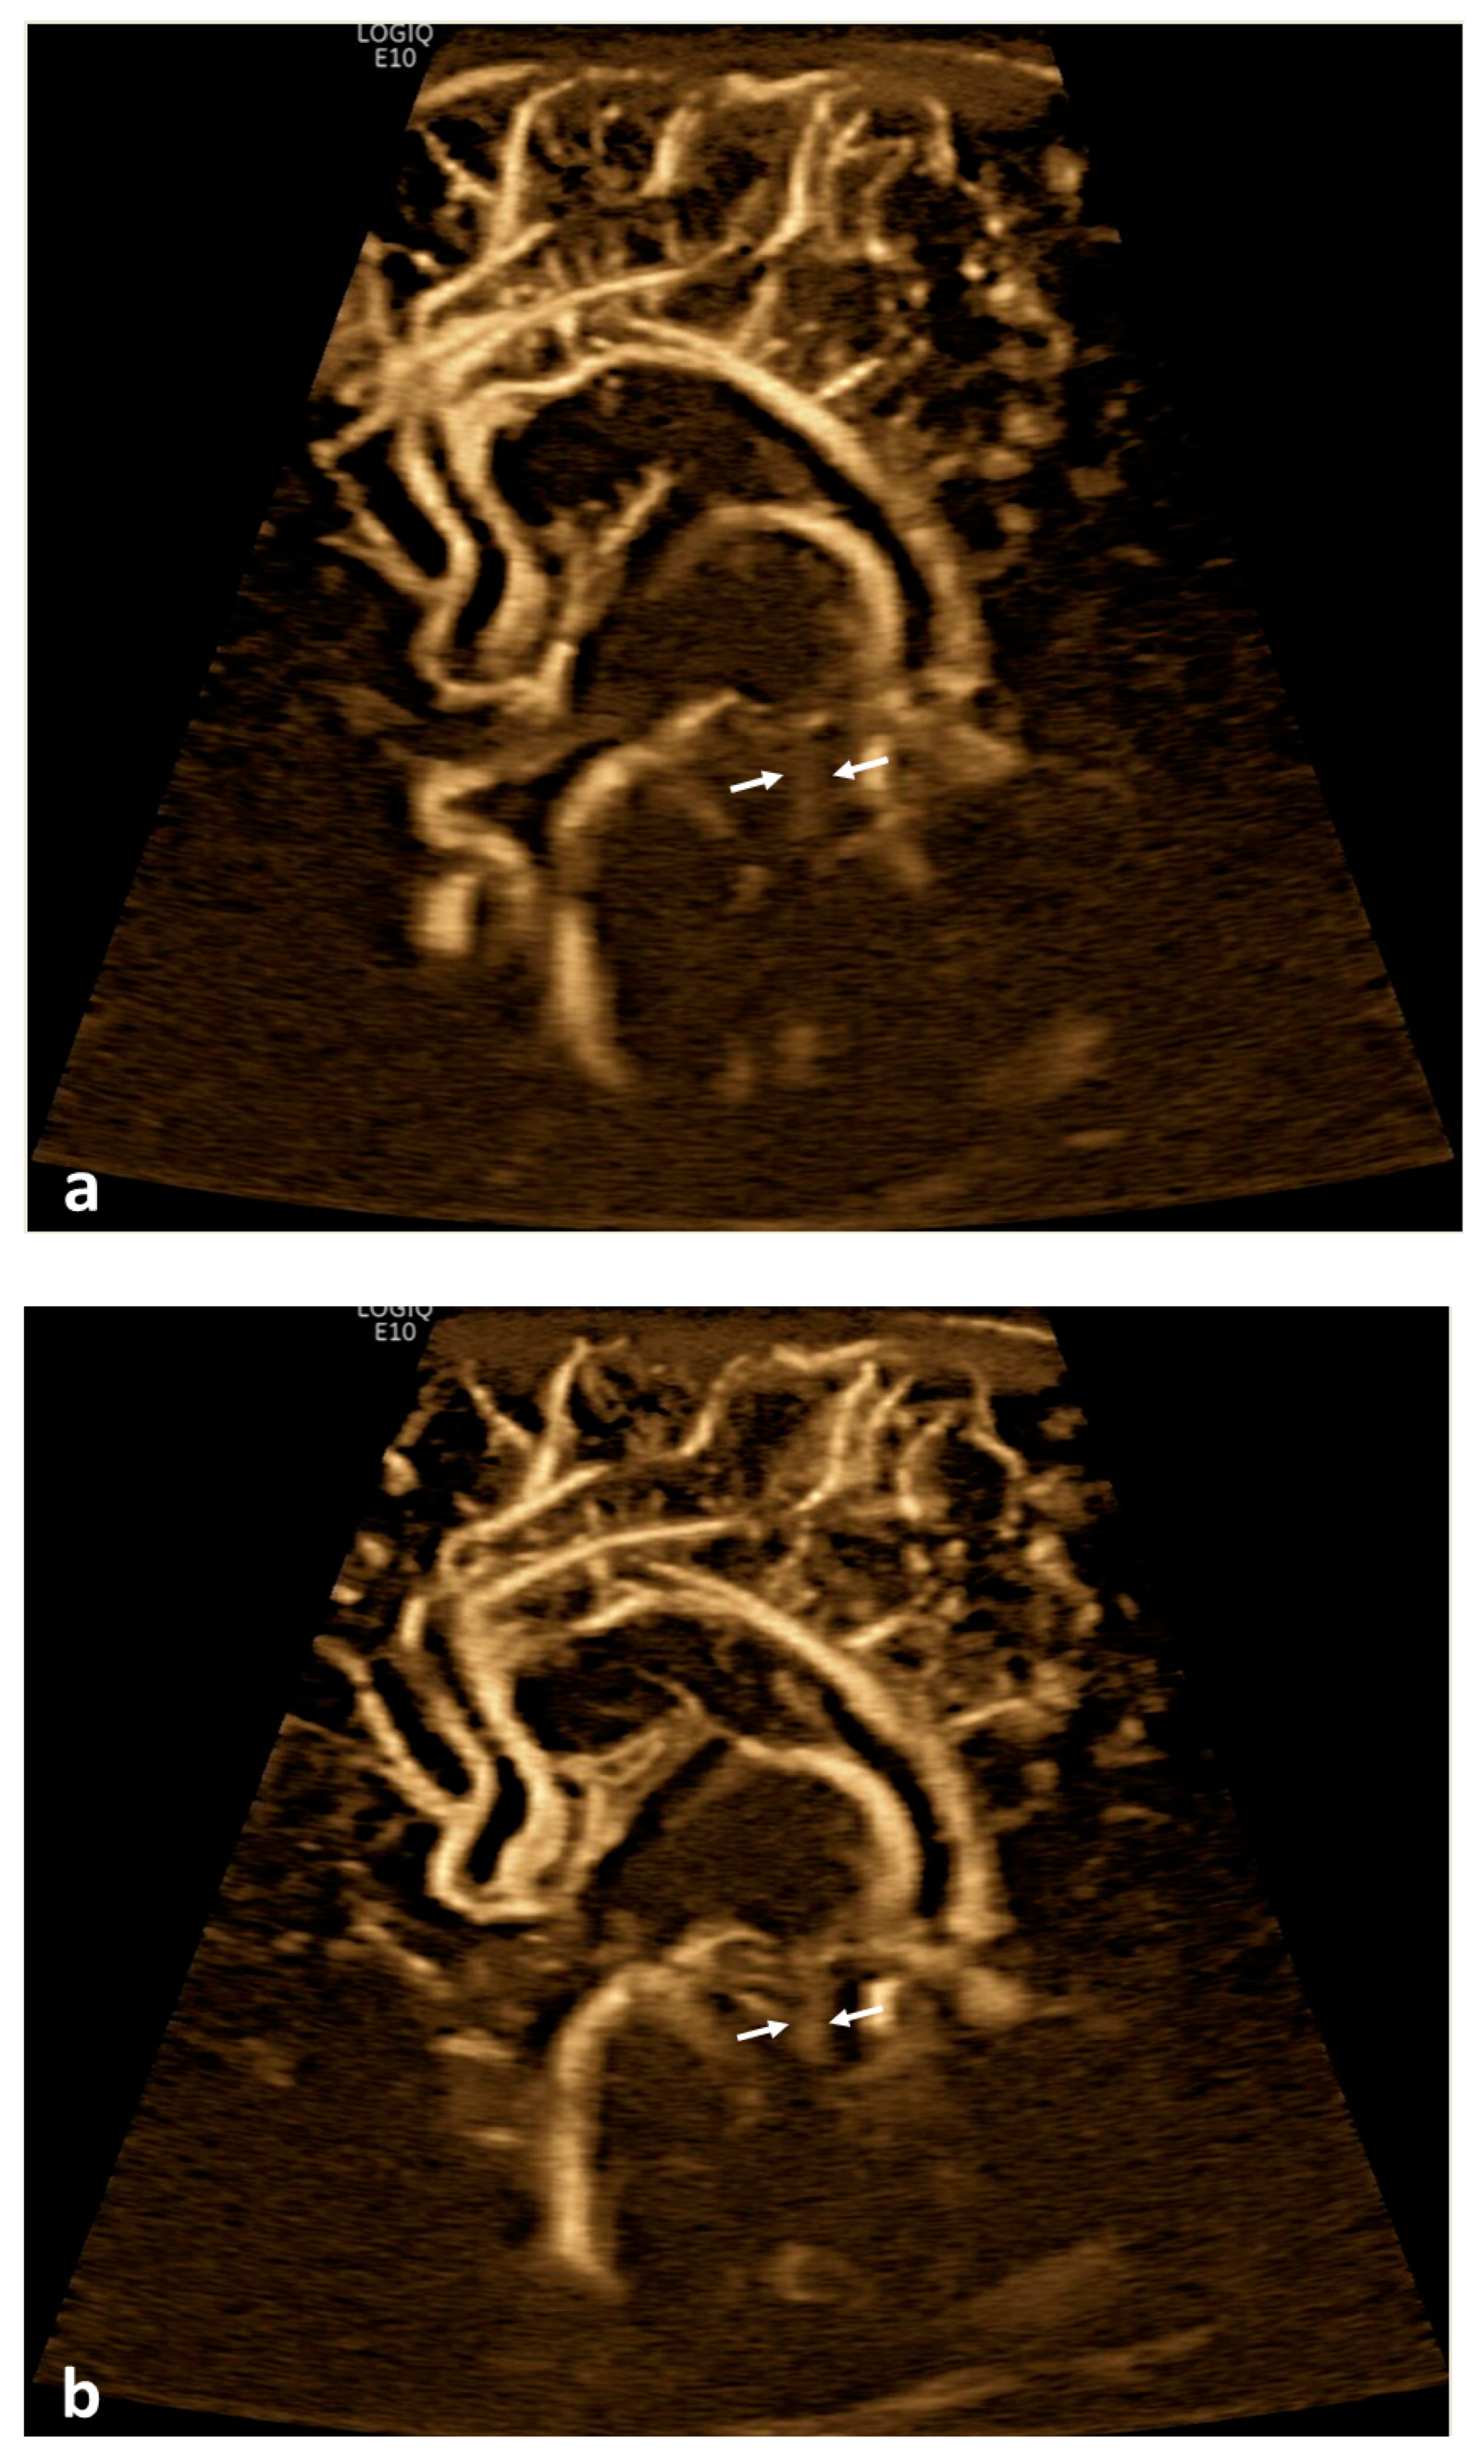

Figure 2.

Cerebrospinal fluid (CSF) flow visualized in a patient with post-hemorrhagic hydrocephalus. A 7-day-old boy with a history of severe intraventricular hemorrhage and ventriculomegaly. Coronal and sagittal grayscale ultrasound shows enlargement in the lateral and third ventricles, as well as evolving choroid plexus hemorrhage and fine granular mobile debris in the ventricles (a–c). The parenchymal evaluation shows grade IV left parieto-occipital periventricular hemorrhage (c). Sagittal B-Flow (d–f) demonstrates turbulent caudocranial CSF flow from the cerebral aqueduct (arrows) into the third ventricle (dotted arrows). The entire clip is provided as Supplemental Material S2.